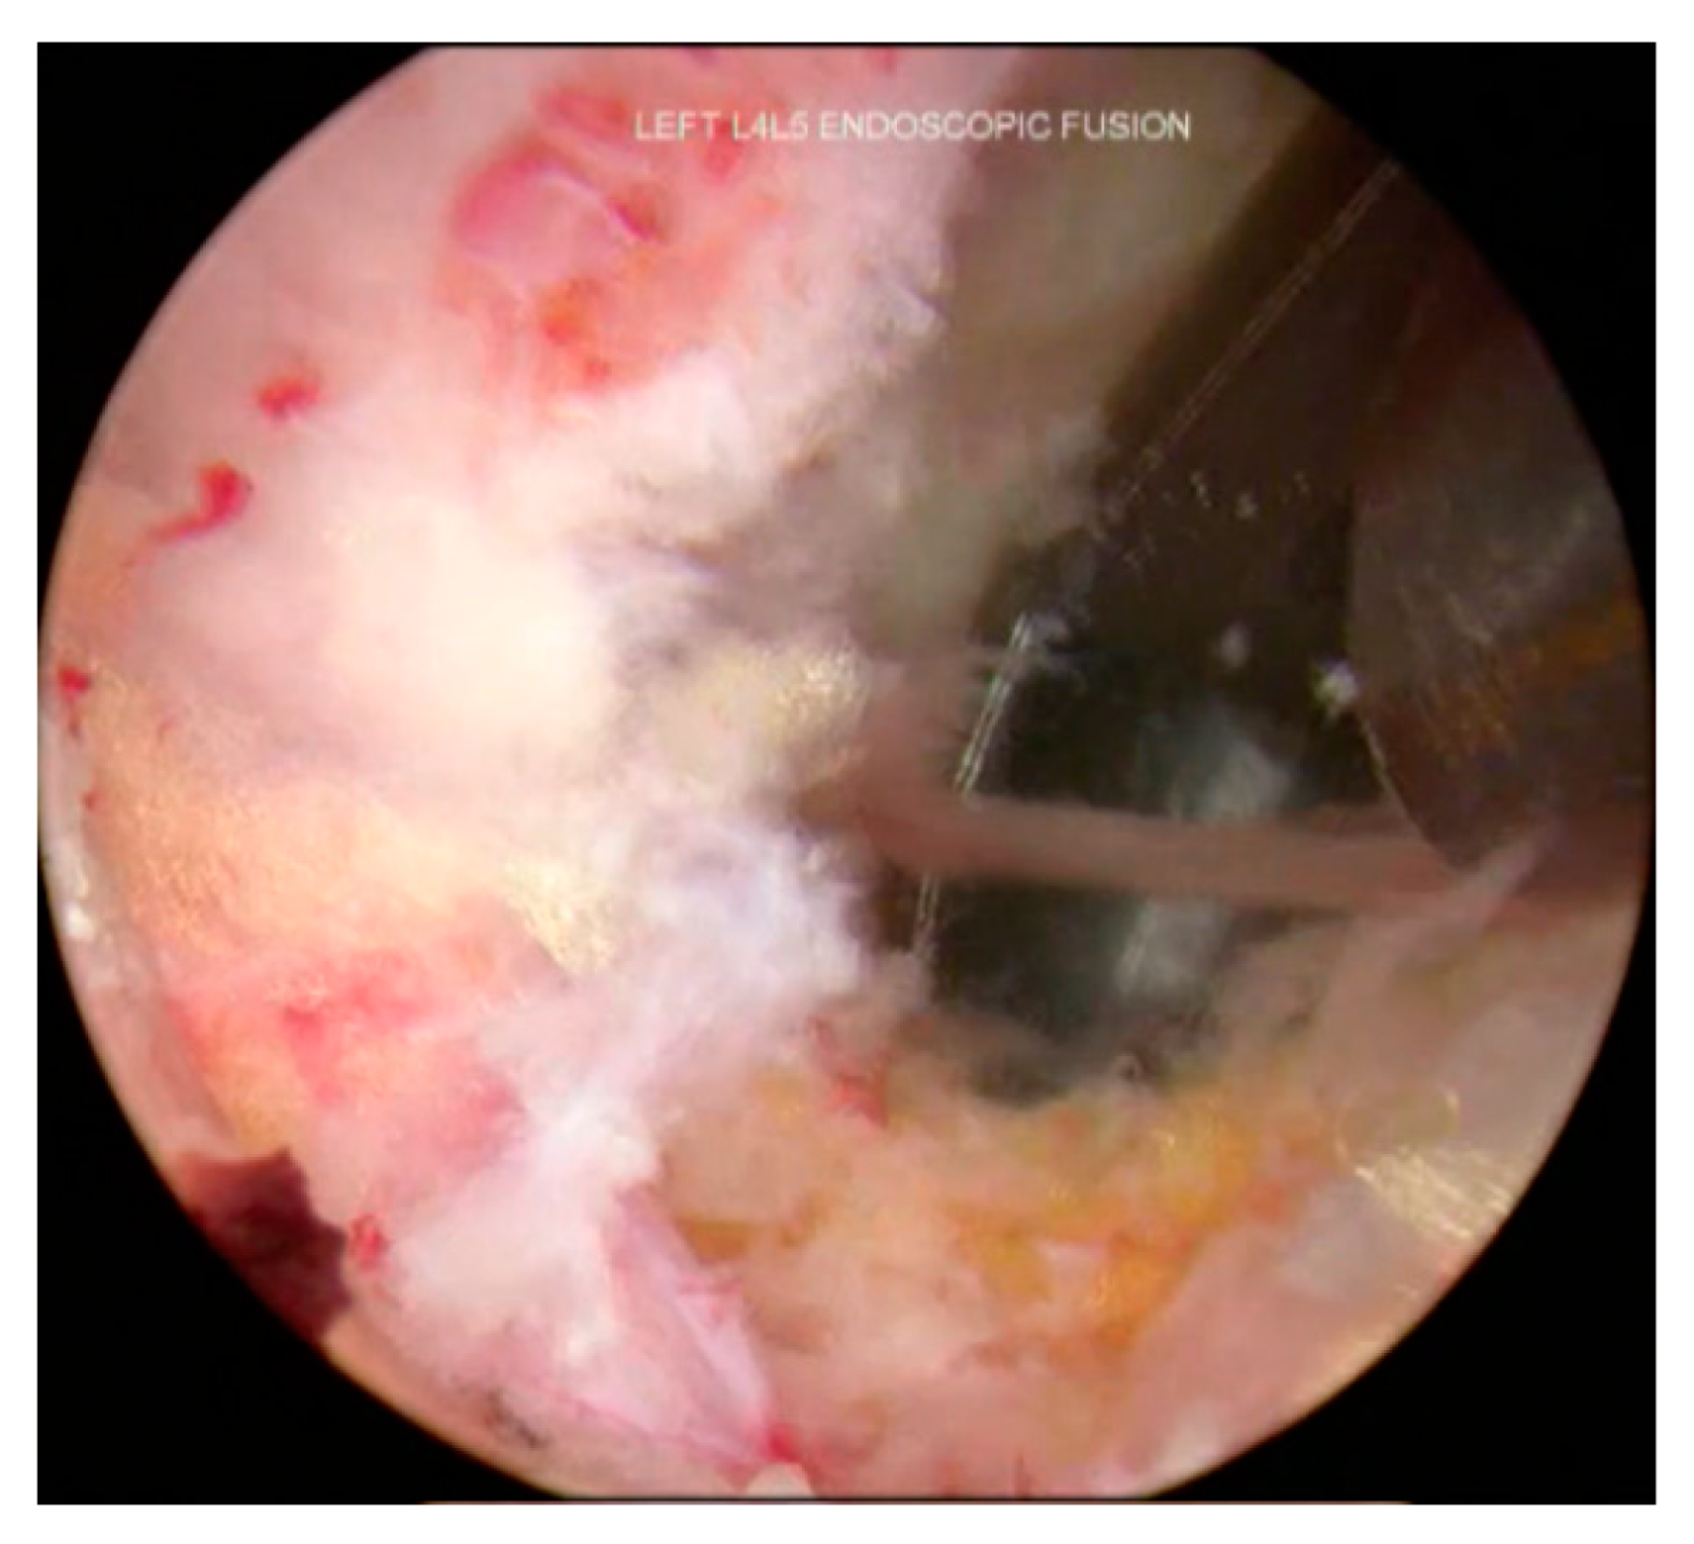

3.8. Cage Insertion with Retractors